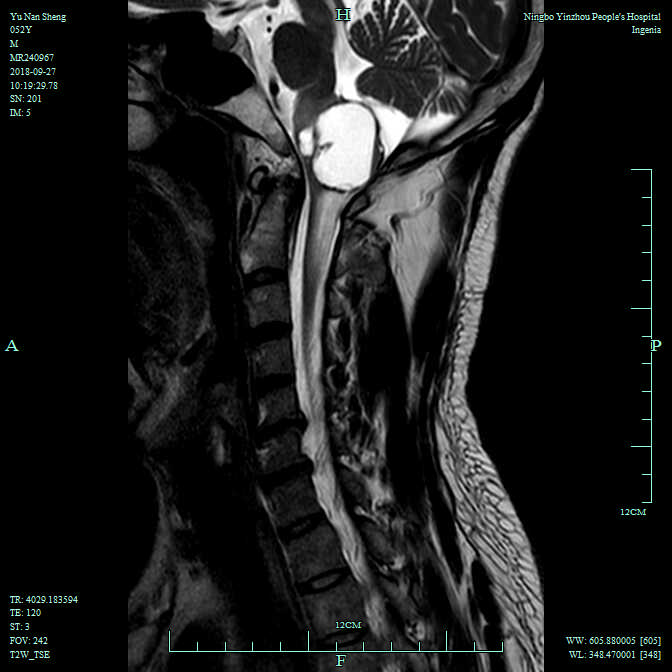

大脑是人体的司令部,掌管着全身的所有活动,而脑干则是其中的生命中枢,其中延髓是脑干最下端与脊髓相连的部分,上接脑桥,控制人的呼吸、血压,被医学界称为“生命禁区”。近日,宁波市鄞州人民医院神经外科高峰主任医师、医学博士接诊了一位来自湖北省恩施土家自治州的52岁农民余老汉,经过检查发现余老汉脑干延髓与颈髓交界处有一个3公分大小的血管母细胞瘤,高峰主任和他的团队历时5个多小时成功完成脑干延髓血管母细胞肿瘤切除手术,该手术是脑干肿瘤手术难度的“塔尖”,标志着该院神经外科显微手术技术达到国内先进水平。

接诊的该院神经外科医生高峰主任医师了解余老汉的病情后,经过全面检查,诊断余老汉为延髓血管母细胞瘤,是神经系统良性肿瘤,手术切除是现今最有效的治疗方法。但脑干肿瘤手术风险极大,尤其是延髓部位的肿瘤,任何细小的手术操作都很容易造成呼吸心跳停止,而且该患者延髓血管母细胞瘤虽为良性肿瘤,但它血供丰富,稍有不慎造成大出血就会造成无法挽回的后果,因此这种类型的肿瘤被神经外科医生戏称为“神经外科医生的杀手”。

10月5日,高峰博士亲自主刀为余老汉进行手术, 手术采取枕下后正中入路,术中高主任在显微镜下精细地分离小脑组织,显露脑干,暴露出长在延髓上的肿瘤,肿瘤已深扎在延髓背侧,囊性部分与周围结构紧密粘连;高峰小心沿着肿瘤与周围组织的界面进行分离,由于处理蒂部时不可避免对延髓的牵拉及刺激,术中心率出现一段时间明显的波动,麻醉师万莉主任及和他的团队沉着冷静地进行调整,手术间充满着紧张的气氛,微小的闪失都会导致患者立即死亡。经过5个多小时紧张精细的手术,肿瘤被完全切除,余老汉术后被送往该院ICU病房24小时持续监护,术后第三天余老汉安返神经外科继续治疗。如今余老汉感到四肢的麻木感开始减轻,术后一周后余老汉在家人帮助下下地活动,可以正常吃饭,生活质量得到了极大改善。

据高峰主任介绍,脑干以往被认为是手术禁区,其中延髓区更被医学界认为是禁区中的禁区。延髓血管母细胞瘤是颅内少见血管性肿瘤,约占脑干肿瘤的1 0%,组织学上属于良性肿瘤,手术切除是现今最有效的治疗方法。延髓肿瘤初期症状常不典型,病人可有不同程度头昏、头痛,后期可出现走路不稳以及后组颅神经麻痹的症状,如吞咽困难、呛咳等等,甚至突发呼吸循环抑制,危及生命。因此如身患此类疾病,最好的办法就是及早就医,及早诊断,及早手术,有不少病人还是能够取得比较满意的疗效。